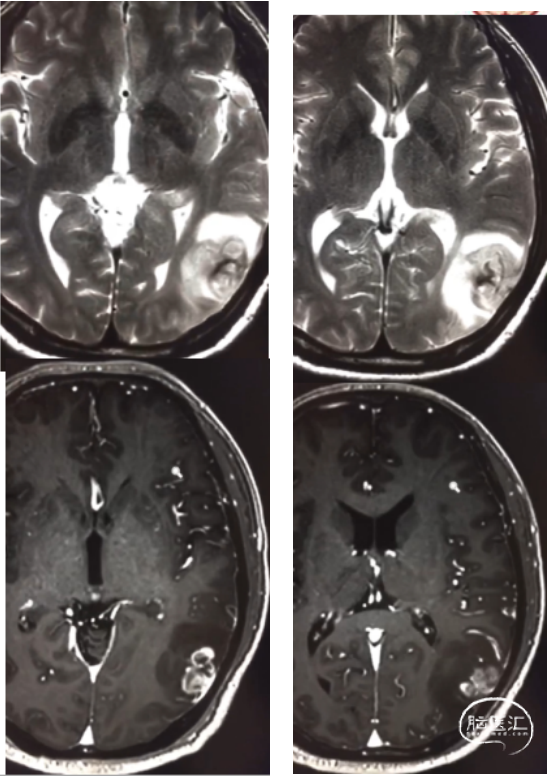

患者为中年男性,因“间断性头痛2月,加重1周”于2020年4月30日入院。入院时神经系统体征(-)。术前诊断为左顶枕叶胶质瘤。